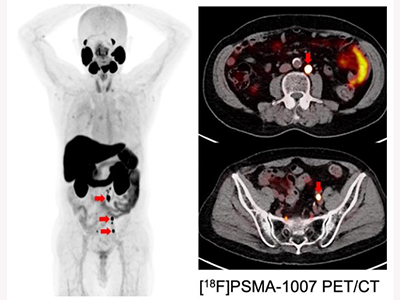

画像はリリースより

海外で承認のβ線核種ルテチウムPSMA治療、Lu-177は国内製造不可・治療抵抗性の課題

近年、狙った標的に結合する化合物に、標識する核種を変えることで、がんの診断から治療まで一貫して実施するセラノスティクス(Theranostics)が注目を集めている。前立腺特異的膜抗原(PSMA)は、PETを用いた画像診断から核医学治療まで展開可能なセラノスティクスの革新的な標的として注目されている。

研究グループはこれまで、独デュッセルドルフ大学のFrederik Giesel教授らとの共同研究を行い、PSMAを標的としたPET画像診断の臨床研究を実施してきた。また、海外ではβ線核種のルテチウム(Lu-177)を用いたPSMA治療がすでに承認されているが、Lu-177は日本国内で製造ができないことや、Lu-177治療抵抗性の患者がいることがわかっている。